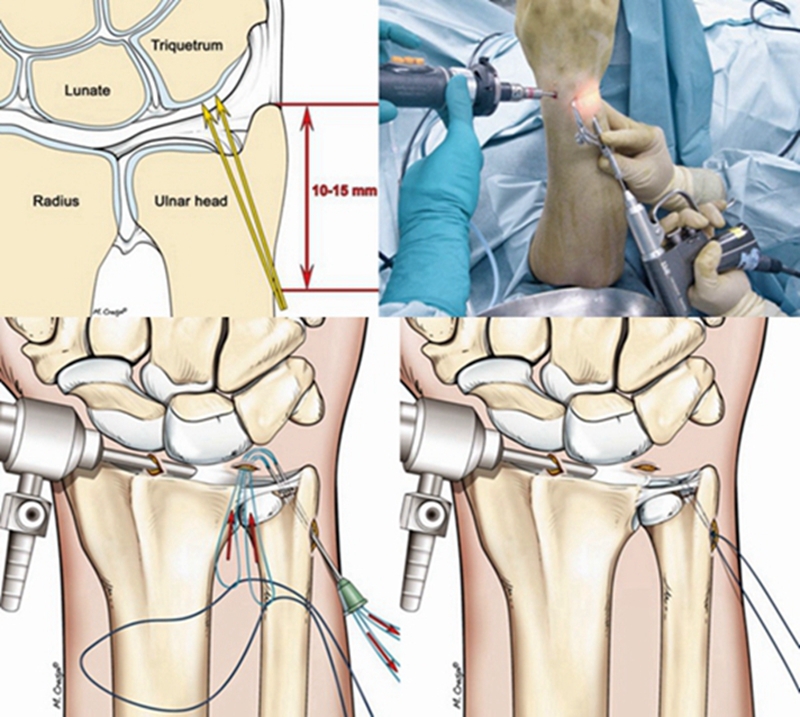

ⅠB型损伤手术治疗多采用缝合修复术。

TFCCⅡ型损伤,对症状持续存在,经保守治疗无效者可行腕关节镜手术。

ⅡA、ⅡB、Ⅱc型损伤:腕关节镜下清创术及软骨成形术;若合并尺骨撞击或尺骨正变异者,行关节镜下清创术结合尺骨头部分磨除术(Wafer术)。